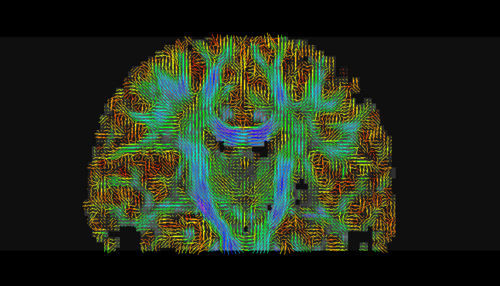

create a DTI (Diffusion Tensor Image) tensor with standard measures like fractional anisotropy (FA), mode and trace,

run tractography and deal with connection maps.

- Tractography panel:

- Connectivity Map panel: